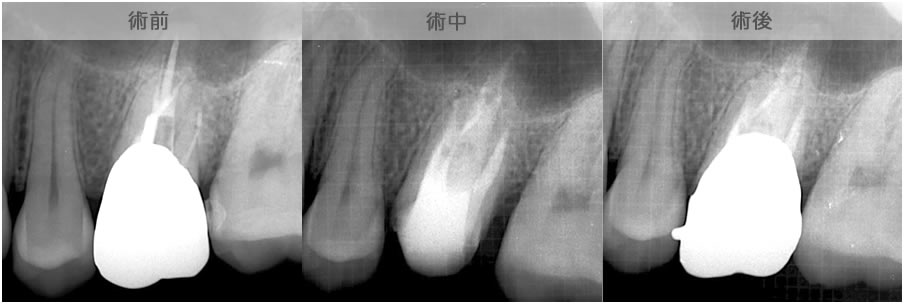

| 治療説明 | 上顎前歯部の根尖部からの排膿があります。歯冠補綴物とメタルコアを除去し、根管治療を行いました。根尖部から根充剤が漏れてはみ出していましたが、X線透過像は消失しました。 |

|---|---|

| 治療場所 | 上顎前歯部 |

| 原因 | 根尖病巣 |

| 治療期間 | 6〜24ヶ月 |

| 治療費用 | 150,000〜300,000円 |

| 治療に伴うリスク | 根管内からの治療で根尖病巣が治らない場合は、外科的に根尖病巣を除去する必要があります。 再根管治療を繰り返す場合、歯根の厚みが薄くなり、歯根破折のリスクが高まります。 |